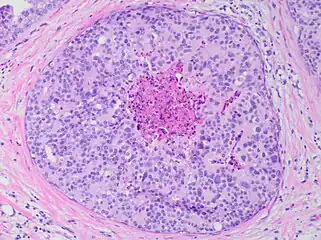

Immunohistochemistry for calponin in ductal carcinoma in situ, highlighting myoepithelial cells around all tumor cells, thereby ruling out invasive ductal carcinoma. Ductal carcinoma in situ with comedo necrosis spanning 30% of its diameter, which is generally regarded as the minimal size to classify it as comedo.[27]

Ductal carcinoma in situ with comedo necrosis spanning 30% of its diameter, which is generally regarded as the minimal size to classify it as comedo.[27]

- Reference for 30% being the most common definition of comedo necrosis by size:

- Harrison, B.T.; Hwang, E.S.; Partridge, A.H.; Thompson, A.M.; Schnitt, S.J. (2019). "Variability in diagnostic threshold for comedo necrosis among breast pathologists: implications for patient eligibility for active surveillance trials of ductal carcinoma in situ". Mod Pathol. 32 (9): 1257–1262. doi:10.1038/s41379-019-0262-4. PMID 30980039. - ↑ Mannu, Gurdeep S.; Bettencourt-Silva, Joao H.; Ahmed, Farid; Cunnick, Giles (2015). "A Nationwide Cross-Sectional Survey of UK Breast Surgeons' Views on the Management of Ductal Carcinoma In Situ". International Journal of Breast Cancer. 2015: 104231. doi:10.1155/2015/104231. PMC 4677188. PMID 26697227.